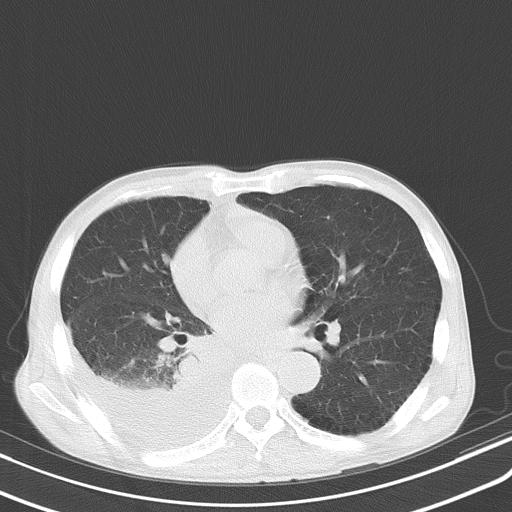

男性 75  咳嗽 一周前发热最高达39

右肺继发型tb并右侧tb性胸腔炎,右侧胸腔大量积液并右下肺膨胀不全,慢支肺气肿、多发肺大泡。建议抽胸水实验室检查并复查排除恶性在占位。

右上肺继发型肺结核,右胸腔中等量积液。

左上肺大泡。

结核的基础上有纵隔淋巴结肿大,右侧有胸水,但右侧纵隔反而窄,说明有肺有不张。

再就是右下肺有块影,和不张混合,还是不能除外肺癌。

1)右肺继发型肺结核。2)左肺胸膜下多发性肺大泡。3)右侧胸腔积液。